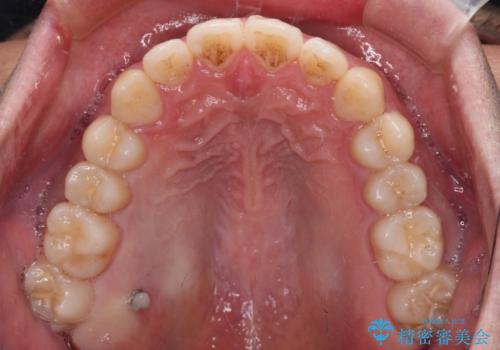

インビザラインで奥歯の咬み合わせと前歯のデコボコを改善

- 前歯のデコボコと奥歯の咬み合わせを気にして来院された患者様です。

前歯のデコボコはインビザラインで十分に対応可能と判断できましたが、咬合力が強いため、臼歯(特に右側)の交叉咬合はインビザライン単体では困難と思われました。

まずはインビザライン単体で矯正治療を開始し、交叉咬合が改善されない場合にはアンカースクリューなどの使用を検討することとしました。

インビザライン単体では右側の交叉咬合を解消することができなかったため、アンカースクリューを併用して咬合を改善させました。